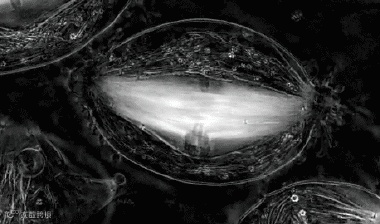

9、这张动图显示的是人类胚胎最早的发育阶段,细胞分裂增殖变化